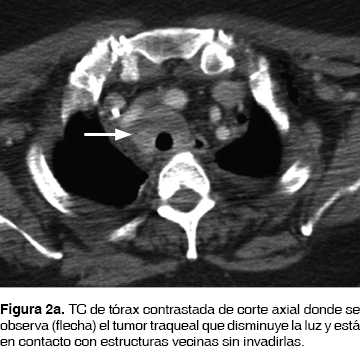

Su padecimiento actual lo inicio seis meses previos a su ingreso con disnea, estridor, con diagnóstico de asma por otra institución, tratada con broncodilatadores, esteroides, con mejoría parcial. La disnea progresó y el estridor en un inicio inspiratorio fue, posteriormente, bifásico con accesos de tos no productiva, con utilización de músculos accesorios para la ventilación. Ingresó al Servicio de Urgencias del Instituto Nacional de Enfermedades Respiratorias Ismael Cosío Villegas (INER), Ciudad de México, con datos de estenosis traqueal; motivo por el cual se le realizó broncoscopia flexible, observado tumor traqueal blanco nacarado, irregular (figura 1) desde el 2do. al 8vo. anillo traqueal (AT), 5 AT libres a la carina principal (CP) que ocasionaba disminución de la luz traqueal en un 90% y se dejó con intubación orotraqueal para permeabilizar la vía aérea. A los dos días le fue realizada una broncoscopia rígida con resección parcial de la tumoración para permeabilizar la vía aérea y toma de biopsia. En el posquirúrgico inmediato presentó enfisema subcutáneo en cuello, cara, tórax y neumotórax bilateral, colocándole sonda torácica bilateral. Por broncoscopia se identificó lesión traqueal, localizada en cara posterior en la unión con cara lateral de 1 cm de longitud a 3 cm de la CP, se dio manejo conservador con intubación orotraqueal ferulizando la lesión traqueal, con ventilación mecánica invasiva por siete días. El Servicio de Patología del INER reportó carcinoma adenoideo quístico. Para estadificarla se realizó TC de tórax (figura 2a, 2b), abdomen, pelvis y cráneo. Fue identificada la tumoración traqueal en tercio medio de la tráquea sin datos de lesiones a distancia. Se retiraron las sondas torácicas.